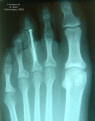

WHAT IS A BUNION?

A bunion is an enlargement of the joint at the base of the big toe—the metatarsophalangeal (MTP) joint—that forms when the bone or tissue at the big toe joint moves out of place. This forces the toe to bend toward the others, causing an often painful lump of bone on the foot. Since this joint carries a lot of the body’s weight while walking, bunions can cause extreme pain if left untreated. The MTP joint itself may become stiff and sore, making even the wearing of shoes difficult or impossible. Bunions– from the Latin "bunio," meaning enlargement–can also occur on the outside of the foot along the little toe, where it is called a "bunionette" or "tailor’s bunion.".